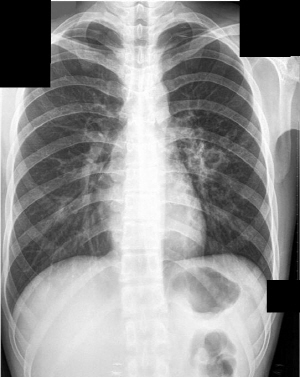

°áÇÙÀº ÀϹÝÀûÀ¸·Î È£Èí±â Áúȯ°ú ºñ½ÁÇÑ ¾ç»óÀ» º¸À̸ç ÀæÀº ±âħ, °¡·¡ µîÀ¸·Î ½ÃÀÛÇÏ¿© ¿­ÀÌ ³ª°í ½ÄÀº¶¡À» È긮¸ç ½±°Ô ÇǷθ¦ ´À³¢°í üÁßÀÌ °¨¼ÒÇÏ´Â µîÀÇ Áõ»óÀÌ ´õÇØÁú ¼ö ÀÖ´Ù. º¸Åë °¨±â¸ö»ì·Î ¿©±â´Â °æ¿ì°¡ ¸¹¾Æ ¿ÀÈ÷·Á °áÇÙÀÌ ÀüÆÄµÉ °¡´É¼ºÀÌ Ä¿Áö°Ô µÈ´Ù. ½ÉÇØÁö¸é ÇǸ¦ ÅäÇϰųª °¡½¿ÅëÁõ, È£Èí°ï¶õÀ¸·Î À̾îÁø´Ù.

´ëü·Î 2ÁÖ ÀÌ»ó ±âħ°ú °¡·¡°¡ Áö¼ÓµÇ°í ¾àÀ» ¸Ô¾îµµ ¼Ò¿ë¾øÀ» ¶§ °áÇٰ˻縦 ¹Þ¾Æº¸´Â °ÍÀÌ ÁÁ´Ù. º¸Åë °áÇÙÀÌ ÆóÁúȯÀÌ¶ó ¿©±â´Â °æ¿ì°¡ ¸¹Àºµ¥ °áÇÙÀº Æó»Ó¸¸ ¾Æ´Ï¶ó È丷, ¸²ÇÁÀý, ôÃß, ³ú, À§Àå, ½ÅÀå µî ÀÎüÀÇ Àü ±â°ü¿¡¼­ ¹ßº´ÇÒ ¼ö ÀÖ´Ù.